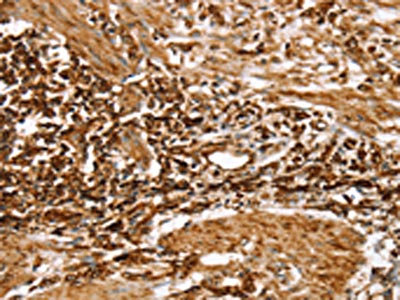

The image on the left is immunohistochemistry of paraffin-embedded Human gastic cancer tissue using CSB-PA327160(RPLP1 Antibody) at dilution 1/25, on the right is treated with fusion protein. (Original magnification: ×200)